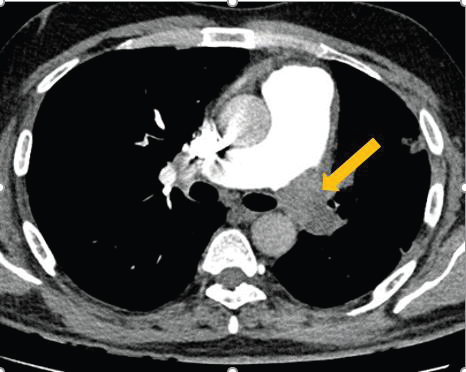

Figure 2:CT pulmonary angiography (CTPA) axial images demonstrate

an intraluminal thrombus causing complete luminal occlusion of the

left main pulmonary artery, consistent with pulmonary embolism.

Despite a total modified Wells score of 1.5 (≤4; PE unlikely) and a

negative age-adjusted D-dimer value of 350, imaging findings confirm

pulmonary embolism.